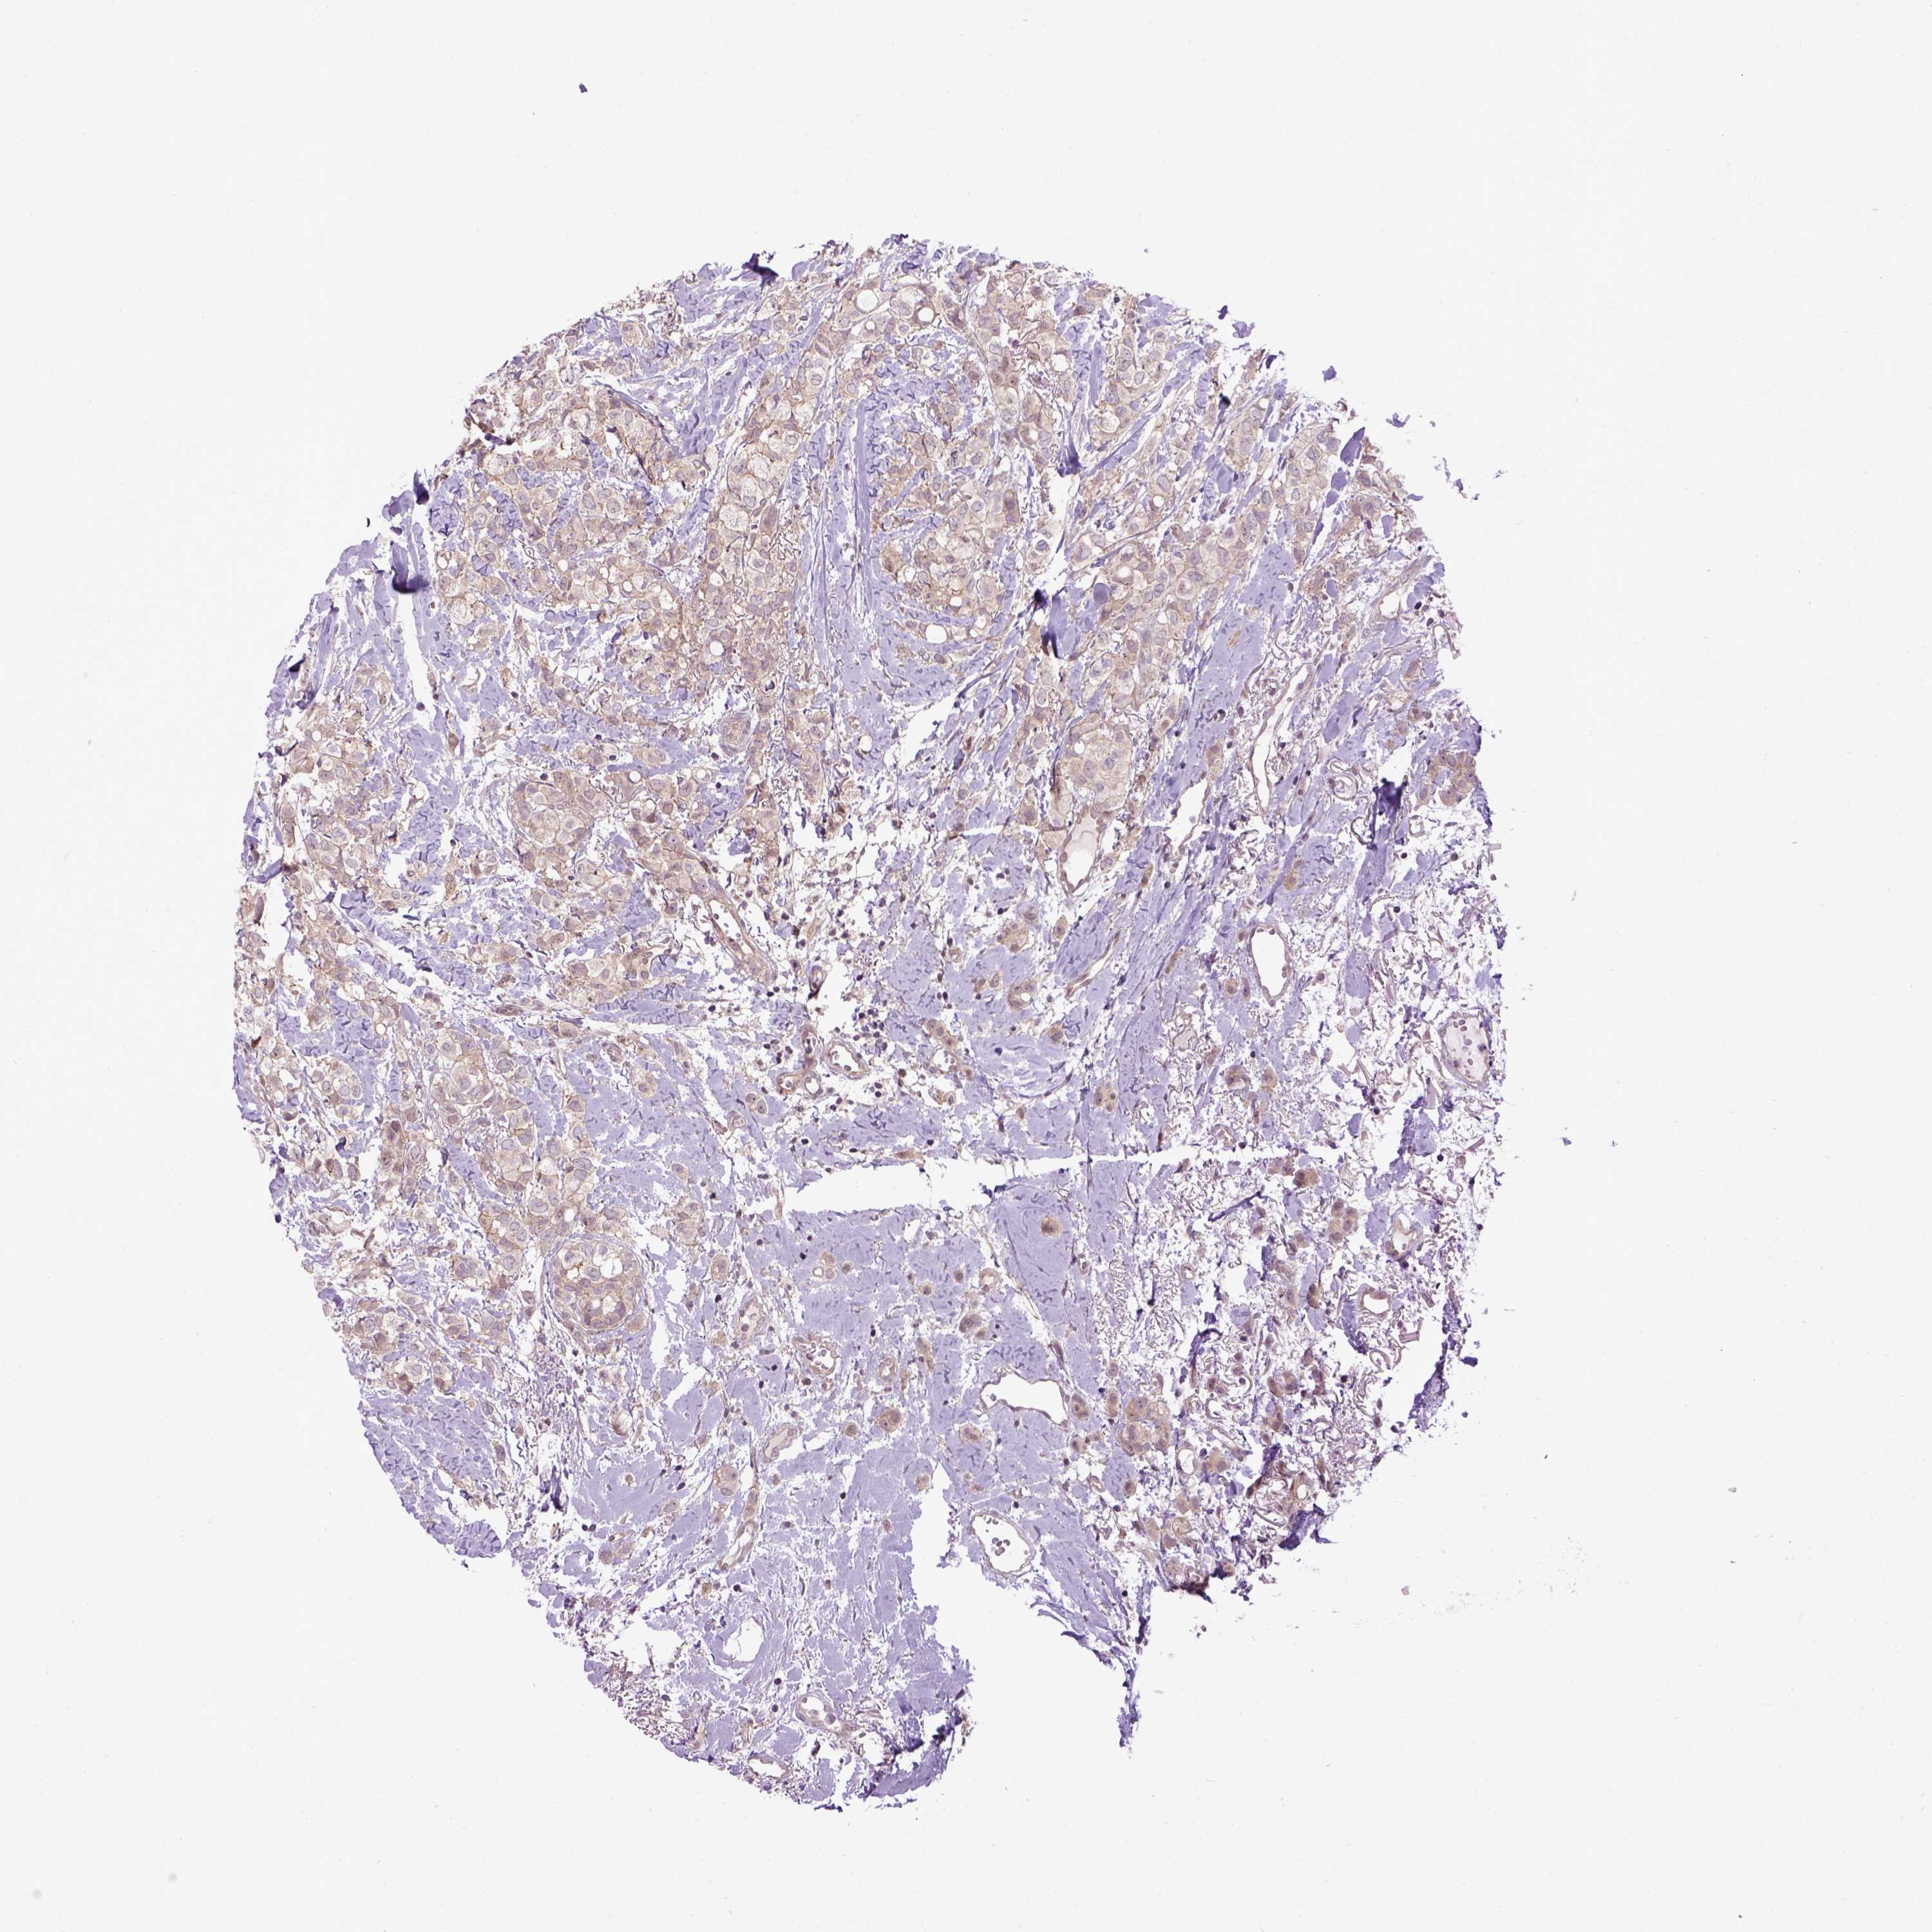

CANCER BREAST CANCER Show tissue menu

BRCA TCGA BRCA VALIDATION PROTEIN EXPRESSION